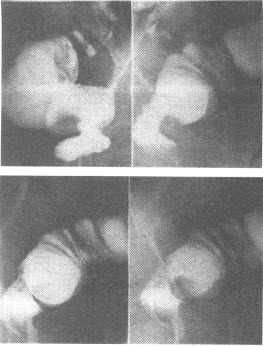

患者,男,25岁。近几年出现吞咽梗阻感,偶出现胸骨后疼痛。行食管吞钡检查如图。

E:典型的X线表现为食管狭窄并其上段极度扩张